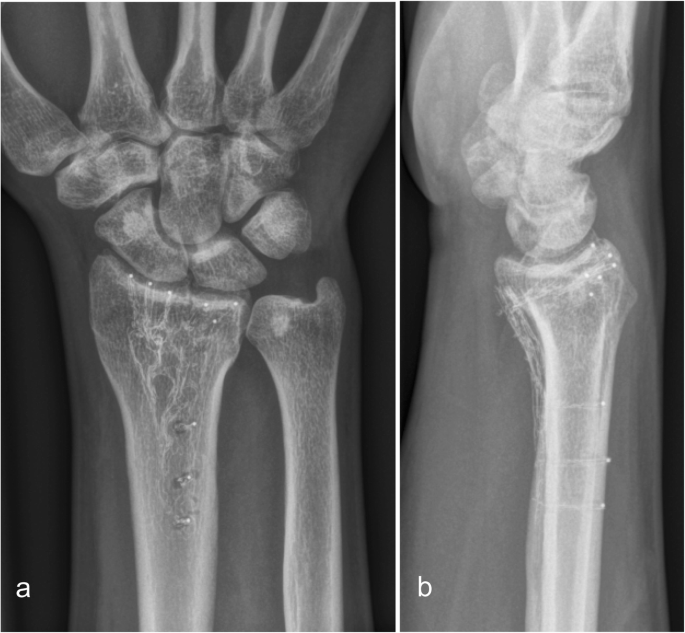

Healing was uneventful and was completed at 6 weeks in all patients (Fig. 1).

At 12 weeks (Fig. 2) and at 1 year (Fig. 3) there was no loss of reduction. No implant failure, screw breakage or loosening was observed. The radiolucent properties of the implant facilitated substantially the assessment of union.